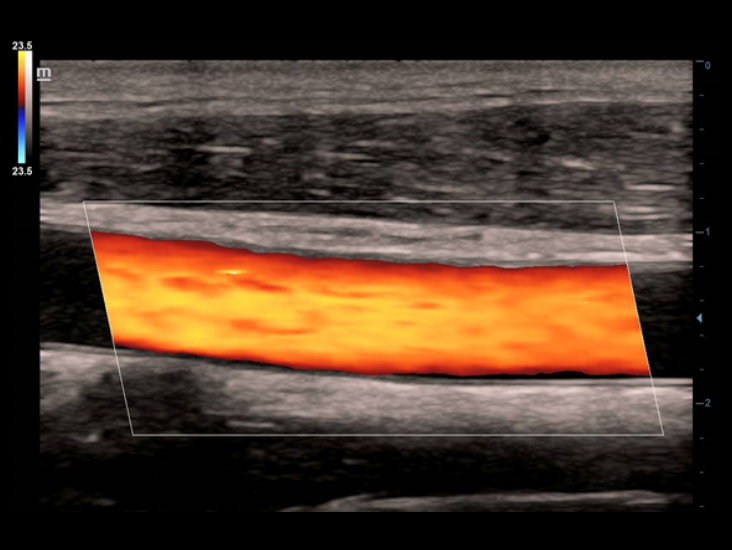

Hervorragende Detailaufl?sung

Unsere Motivation bei Mindray ist es, die moderne Medizintechnik durch zukunftsorientierte Techno-logien zu verbessern. Mit seinem Full HD-Monitor, bew?hrten Ultraschalltechnologien und einer optimierten Schallkopf-Familie bietet das DC-40 mit Full HD eine hervorragende Bildqualit?t. Sie verbessert ein breites Spektrum klinischer Anwendungen.

Diese bew?hrten Ultraschalltechnologien sorgen f├╝r eine h?here Diagnosequalit?t:

- iClear (Rauschunterdr├╝ckungs-Technologie)

- PSH (Harmonic Imaging mit Phasenverschiebung)

- iBeam: (Spatial-Compounding)

Der Einsatz anerkannter Bildgebungstechnologien macht das DC-40 mit Full HD sehr leistungsstark und hochwertig. Sie sind erfolgreich aus etablierten Ultraschallsystemen migriert worden. Eine clevere Kombination von Ultraschallsonden mit spezialisierten Schallk?pfen unterst├╝tzt erstklassige Ergebnisse in einem breiten Anwendungsspektrum. Mit Hilfe der Breitband-Schallk?pfe l?sst sich eine Vielzahl an Patiententypen erfolgreich untersuchen.